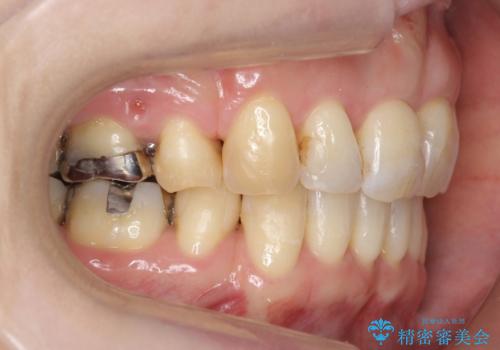

40代の矯正 出っ歯、歯のがたがた

奥歯のかみ合わせのずれと、前歯のがたつきがありました。

上下左右の小臼歯を抜歯しています。

叢生も著しく、少し年齢が上がってからの矯正治療となり、結果ブラックトライアングルが出てしまいましたが、並びの改善で非常に満足していただけました。